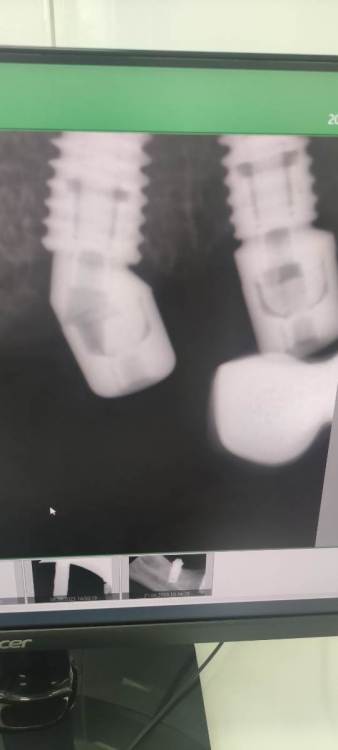

NazranDantist Опубликовано 21 октября, 2023 Поделиться Опубликовано 21 октября, 2023 Сегодня с утра зашел на осмотр пациент, тоже примерно пол года работе, "осстем" 4.0 с консолью, пока не треснул:)) 1 Ссылка на комментарий

NazranDantist Опубликовано 21 октября, 2023 Поделиться Опубликовано 21 октября, 2023 4 часа назад, Женька сказал: @NazranDantist смело) Часто так делаю). Средняя ширина премоляра 5 мм, как установить в этой области 2 Импланта не понимаю, особенно если расстояние немного уменьшилось со временем. Ссылка на комментарий